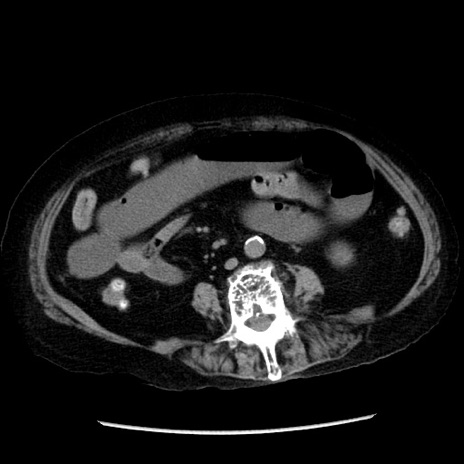

症例14(横断像)

【症例】 90歳代女性

【主訴】 腹痛・嘔吐

【現病歴】今朝から左側腹部痛を認めた。 経過観察していたが、嘔吐を認めたため来院。

【既往歴】 子宮癌術後

【身体所見】 意識清明、BP 127/54mmHg、P 98bpm Sp02 95%(RA)、BT 35.8°C、腹部平坦・軟腸ぜん動音聴取良好、右下腹部圧痛(+) 反跳痛なし

【データ】WBC 9800、CRP 0.46